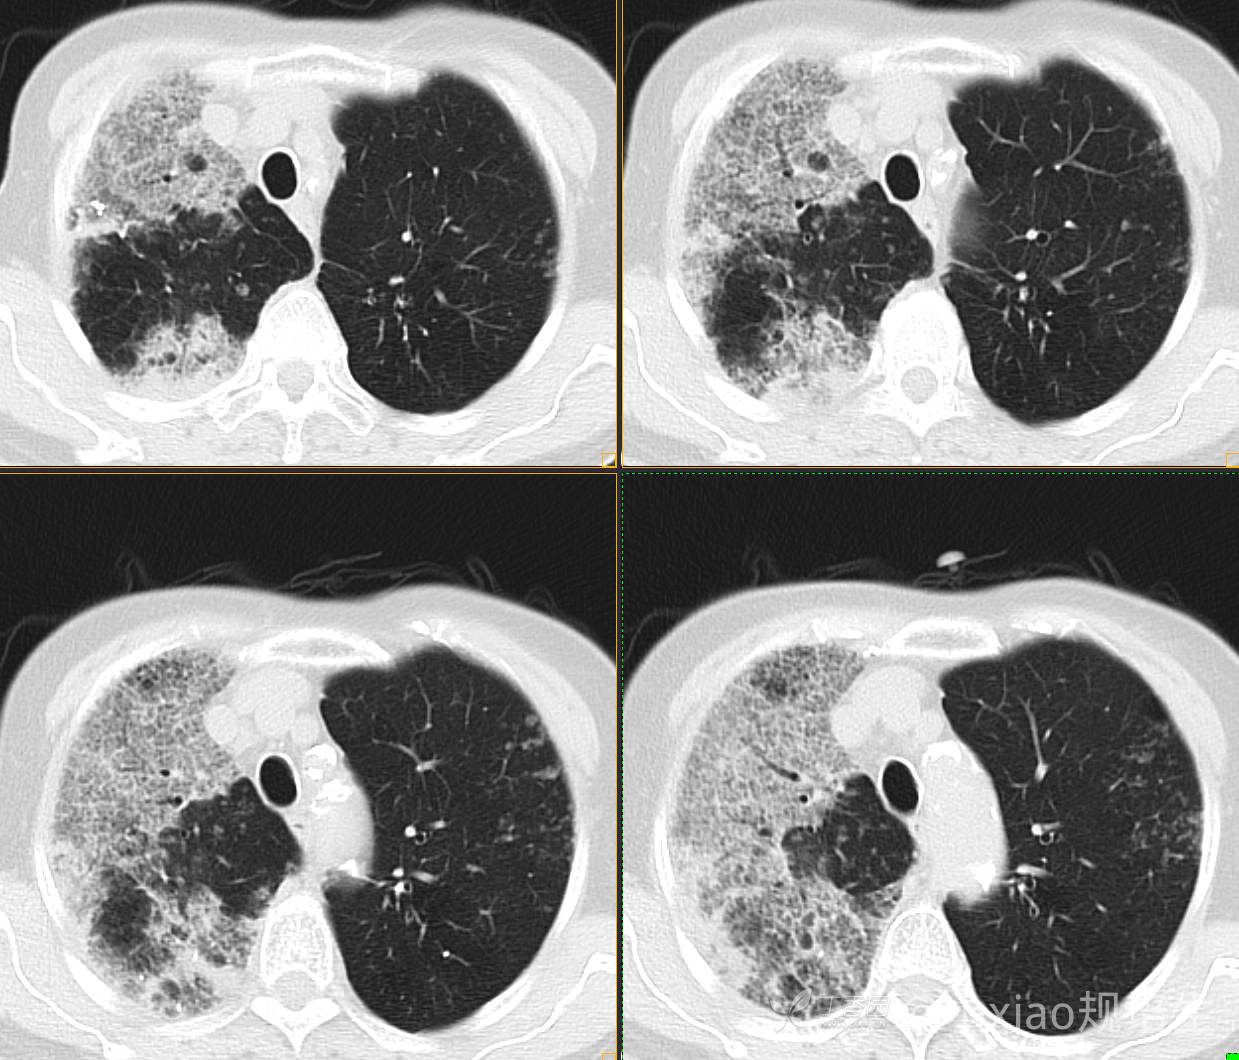

患者,女,89岁

咳嗽,咳痰一月余